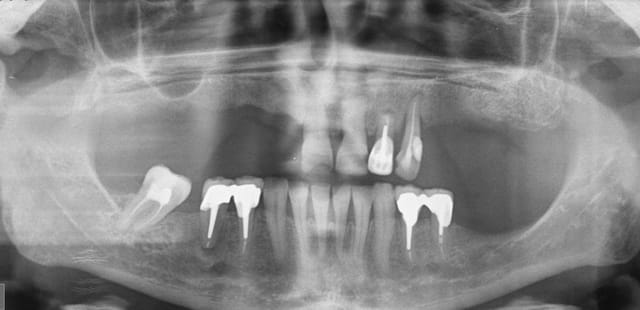

quel serait votre attitude thérapeutique quant aux 45 et 22 ?

en sachant que son opération est prévue le 01/09.

Impossible de donner une réponse définitive sans plus de données, mais rapidement, d'après les radios :

Je laisse 22, le risque est essentiellement mécanique.

Pour 45, si asymptomatique depuis de nombreuses années, je laisse aussi.

Surveillance radiologique bien sûr, et stabilisation occlusale de 23.

patiente diabétique,

aucune symptomatologie bucco-dentaire

sauf que le radiologue qui a fait la pano ( ordo faite par le chir ) note image apicale au niveau de 45 et de 22.

en l'état actuel des choses 22, 45 et 23 sont à extraire ce qui va sans doute amener à modifier le plan de traitement prothétique et envisager d'extraire d'autres dents ??